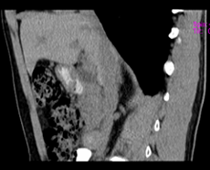

患者,男,57,常年不吃午饭,近一个月来腹部隐痛,无明显黄疸,明天进行增强扫描,图象另上传,麻烦各位帮忙一起看看讨论讨论

肝外胆管扩张,胰头增大,肠系膜上静脉似有包埋征象。

考虑:胰头占位性病变,建议增强进一步检查。

肝内外胆管扩张,胆管未端阻塞,建议mri检查

考虑肝总管或胆总管占位性病变,建议mrcp或ercp.

胰头增大,胆总管增宽,考虑胰头癌可能性大,明天看增强片有助诊断.